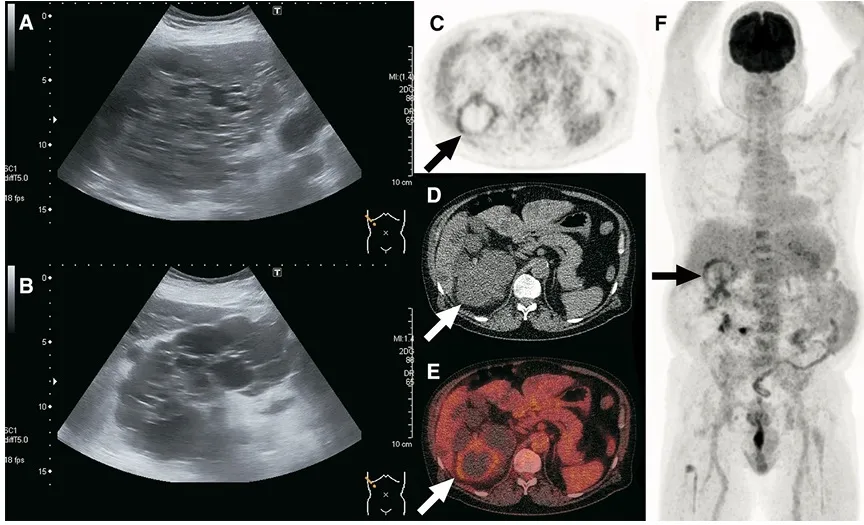

📚 Na série de casos da imagem abaixo (**[link](https://link.springer.com/article/10.1007/s40336-017-0261-8)**), é possível ver como o PET/CT-FDG orienta a conduta e modifica o manejo em infecções renais e hepáticas na DRPAD.

TC ou RM com contraste podem identificar novo cisto complexo, mas geralmente não diferenciam sangue de pus no interior do cisto.

Achados como realce de parede, espessamento, gás intralesional ou alterações inflamatórias pericísticas aumentam a probabilidade de infecção.

O 18F-FDG PET/CT surge como ferramenta de maior especificidade, útil para localizar o(s) cisto(s) infectado(s) e definir o alvo da punção.